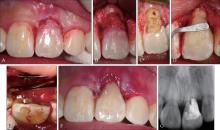

Patel K, Foschi F, Pop I, et al. The use of intentional replantation to repair an external cervical resorptive lesion not amenable to conventional surgical repair[J]. Prim Dent J, 2016, 5(2): 78-83.

Patel S, Foschi F, Condon R, et al. External cervical resorption: part 2—management[J]. Int Endod J, 2018, 51(11): 1224-1238.

Garrido I, Abella F, Ordinola-Zapata R, et al. Combined endodontic therapy and intentional replantation for the treatment of palatogingival groove[J]. J Endod, 2016, 42(2): 324-328.